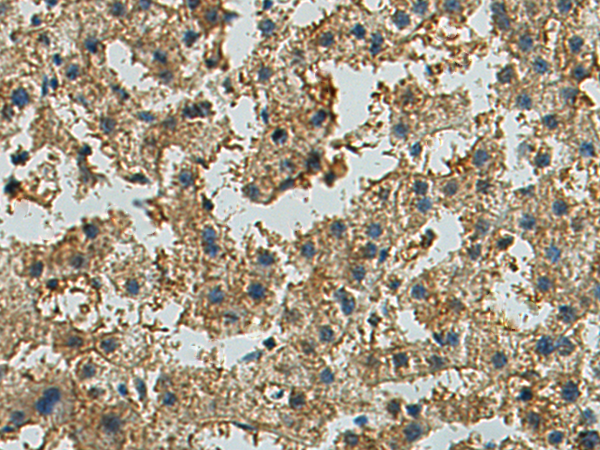

分类: 科研抗体货号: P04629别名: EK4; ETK; HEK; ETK1; HEK4; TYRO4应用: IHC反应种属: Human, Mouse, Rat